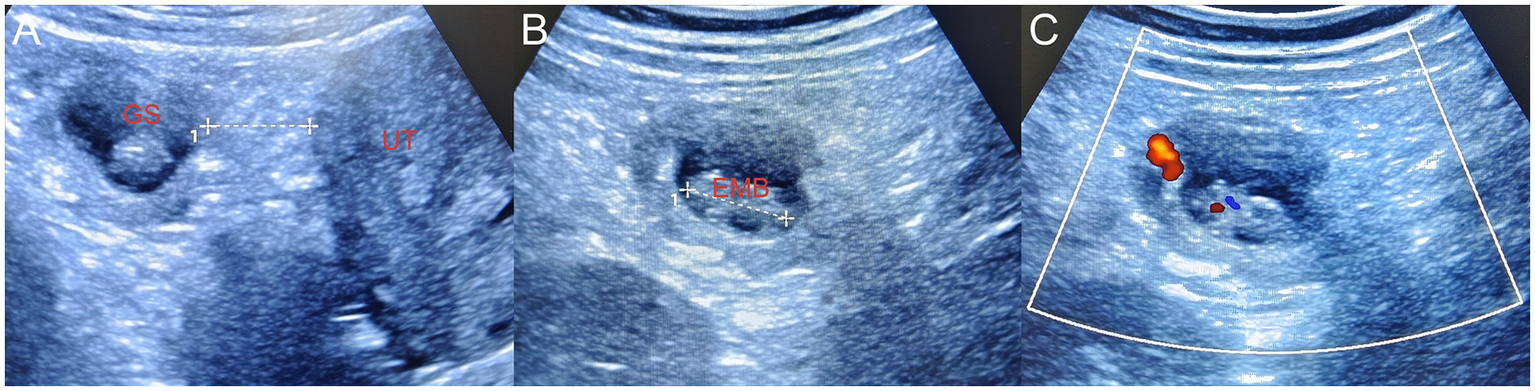

Figure 3

(A) During laparoscopy surgery, the suspicious mass on the omentum was flipped to the left pelvic wall. Bedside ultrasonography revealed a primary omentum pregnancy, and the gestational sac was located approximately 2.5 cm away from the uterus. (B) The length of the embryo was approximately 2.1 cm. (C) CDFI demonstrated the primitive cardiac tube pulsation of the embryo. Since the abdominal and pelvic hemorrhage had been cleared during the surgery, no surrounding effusion was displayed. GS, gestational sac; EMB, embryo; UT, uterus, CDFI, color Doppler flow imaging.

Intraoperatively, approximately 800 mL of dark red blood and blood clots were found in the abdominal and pelvic cavity. The uterine surface was smooth, with adhesion bands formed between the posterior uterine wall and the pelvic floor and partial adhesion of the intestine to the pelvic wall. The bilateral fallopian tubes and ovaries appeared normal with no visible ruptures, and no tissue obstruction was observed at the fimbriated ends of the bilateral fallopian tubes. A 50 mm × 40 mm mass was found on the omentum above the uterus, with no purple-blue appearance on the surface. An intraoperative consultation with the ultrasound department was requested. Ultrasound with a disposable sterile probe cover revealed no GS within the uterus. The suspicious omentum mass was moved toward the left pelvic wall, and ultrasound guidance revealed a GS with an echo of an embryo and fetal heartbeat at the left pelvic wall mass, confirming an OP (Figure 3). An abdominal surgeon was asked to assist in the surgery, and the intra-AP tissue and a portion of the omentum were resected. On examination of the resected omentum specimen, obvious chorionic villi tissue was visible (Figure 4). The postoperative diagnosis was OP with intra-abdominal hemorrhage. The surgery was successful, and the patient was safely taken back to the ward with no bleeding from the incision.